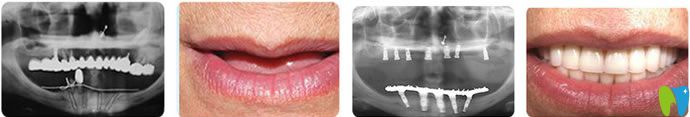

本院手術(shù)網(wǎng)友分享